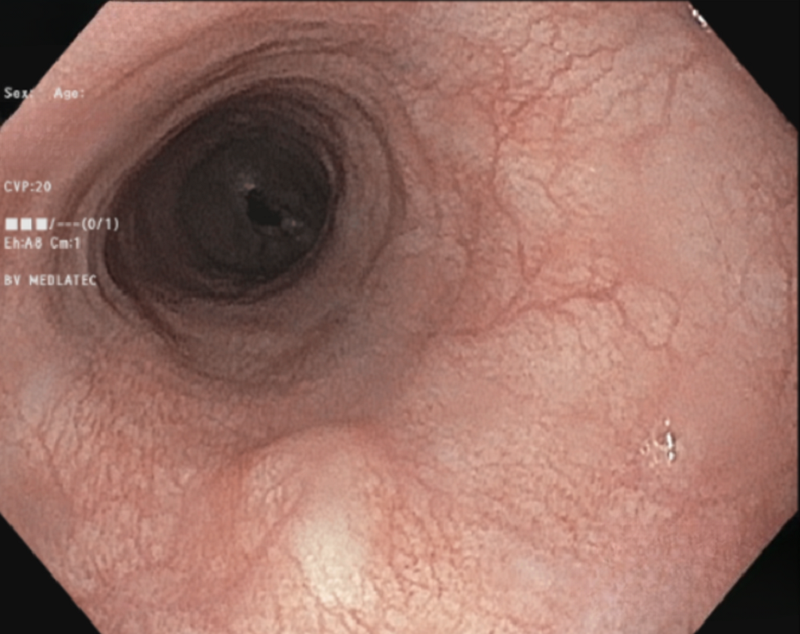

Nội soi đại tràng cho kết quả viêm đại trực tràng, trĩ nội độ II. Hình ảnh nội soi thực quản - dạ dày - tá tràng ghi nhận tại vị trí cách cung răng trên khoảng 33cm có tổn thương lồi kích thước khoảng 0.7cm, bơm hơi căng không biến mất, bề mặt nhẵn, màu sắc giống niêm mạc xung quanh, thăm bằng kìm thấy mềm, di động.

Phát hiện khối u ở thực quản nhờ... uống bia- Ảnh 1.

Nội soi thực quản - dạ dày phát hiện tổn thương lồi dưới niêm mạc thực quản